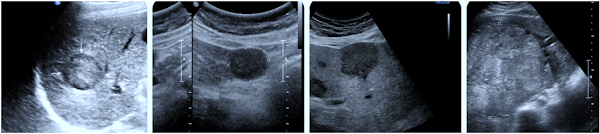

- Demonstrates two well-defined hypoechoic nodules separated by normal tissue—classic multifocal presentation

- Multiple small, heterogeneous hypoechoic to isoechoic lesions scattered across the liver, demonstrating size and echogenic variation

- Larger hypoechoic nodule seen alongside smaller satellite lesions—bi-lobar involvement possible in advanced disease .

- Dense cluster of nodules with varied echotexture; coexisting portal flow abnormalities may suggest vascular invasion .